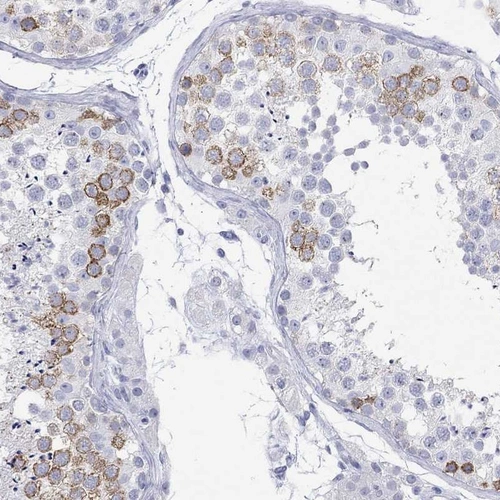

Immunohistochemistry analysis in human testis and rectum tissues using Anti-MAGEB6 antibody. Corresponding MAGEB6 RNA-seq data are presented for the same tissues.